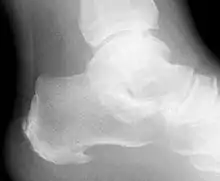

Radiographie du calcanéum humain.

- Os de la rangée proximale du tarse qui forme le talon.